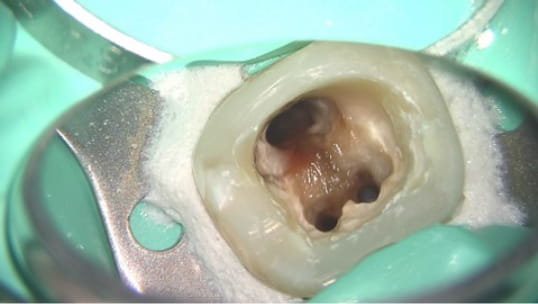

治療中に歯の中に唾液が入ってしまったり、滅菌・消毒されてない器具で歯の中を触ったりすると、

治療しているにも関わらず、逆に病気を作り出しています。

治療の最初から最後まで細菌が入らない環境にしてはじめて精密な治療が意味あるものになります。

当院ではラバーダム使用など、エビデンスに基づいた万全の細菌感染対策を行って治療を行っております。